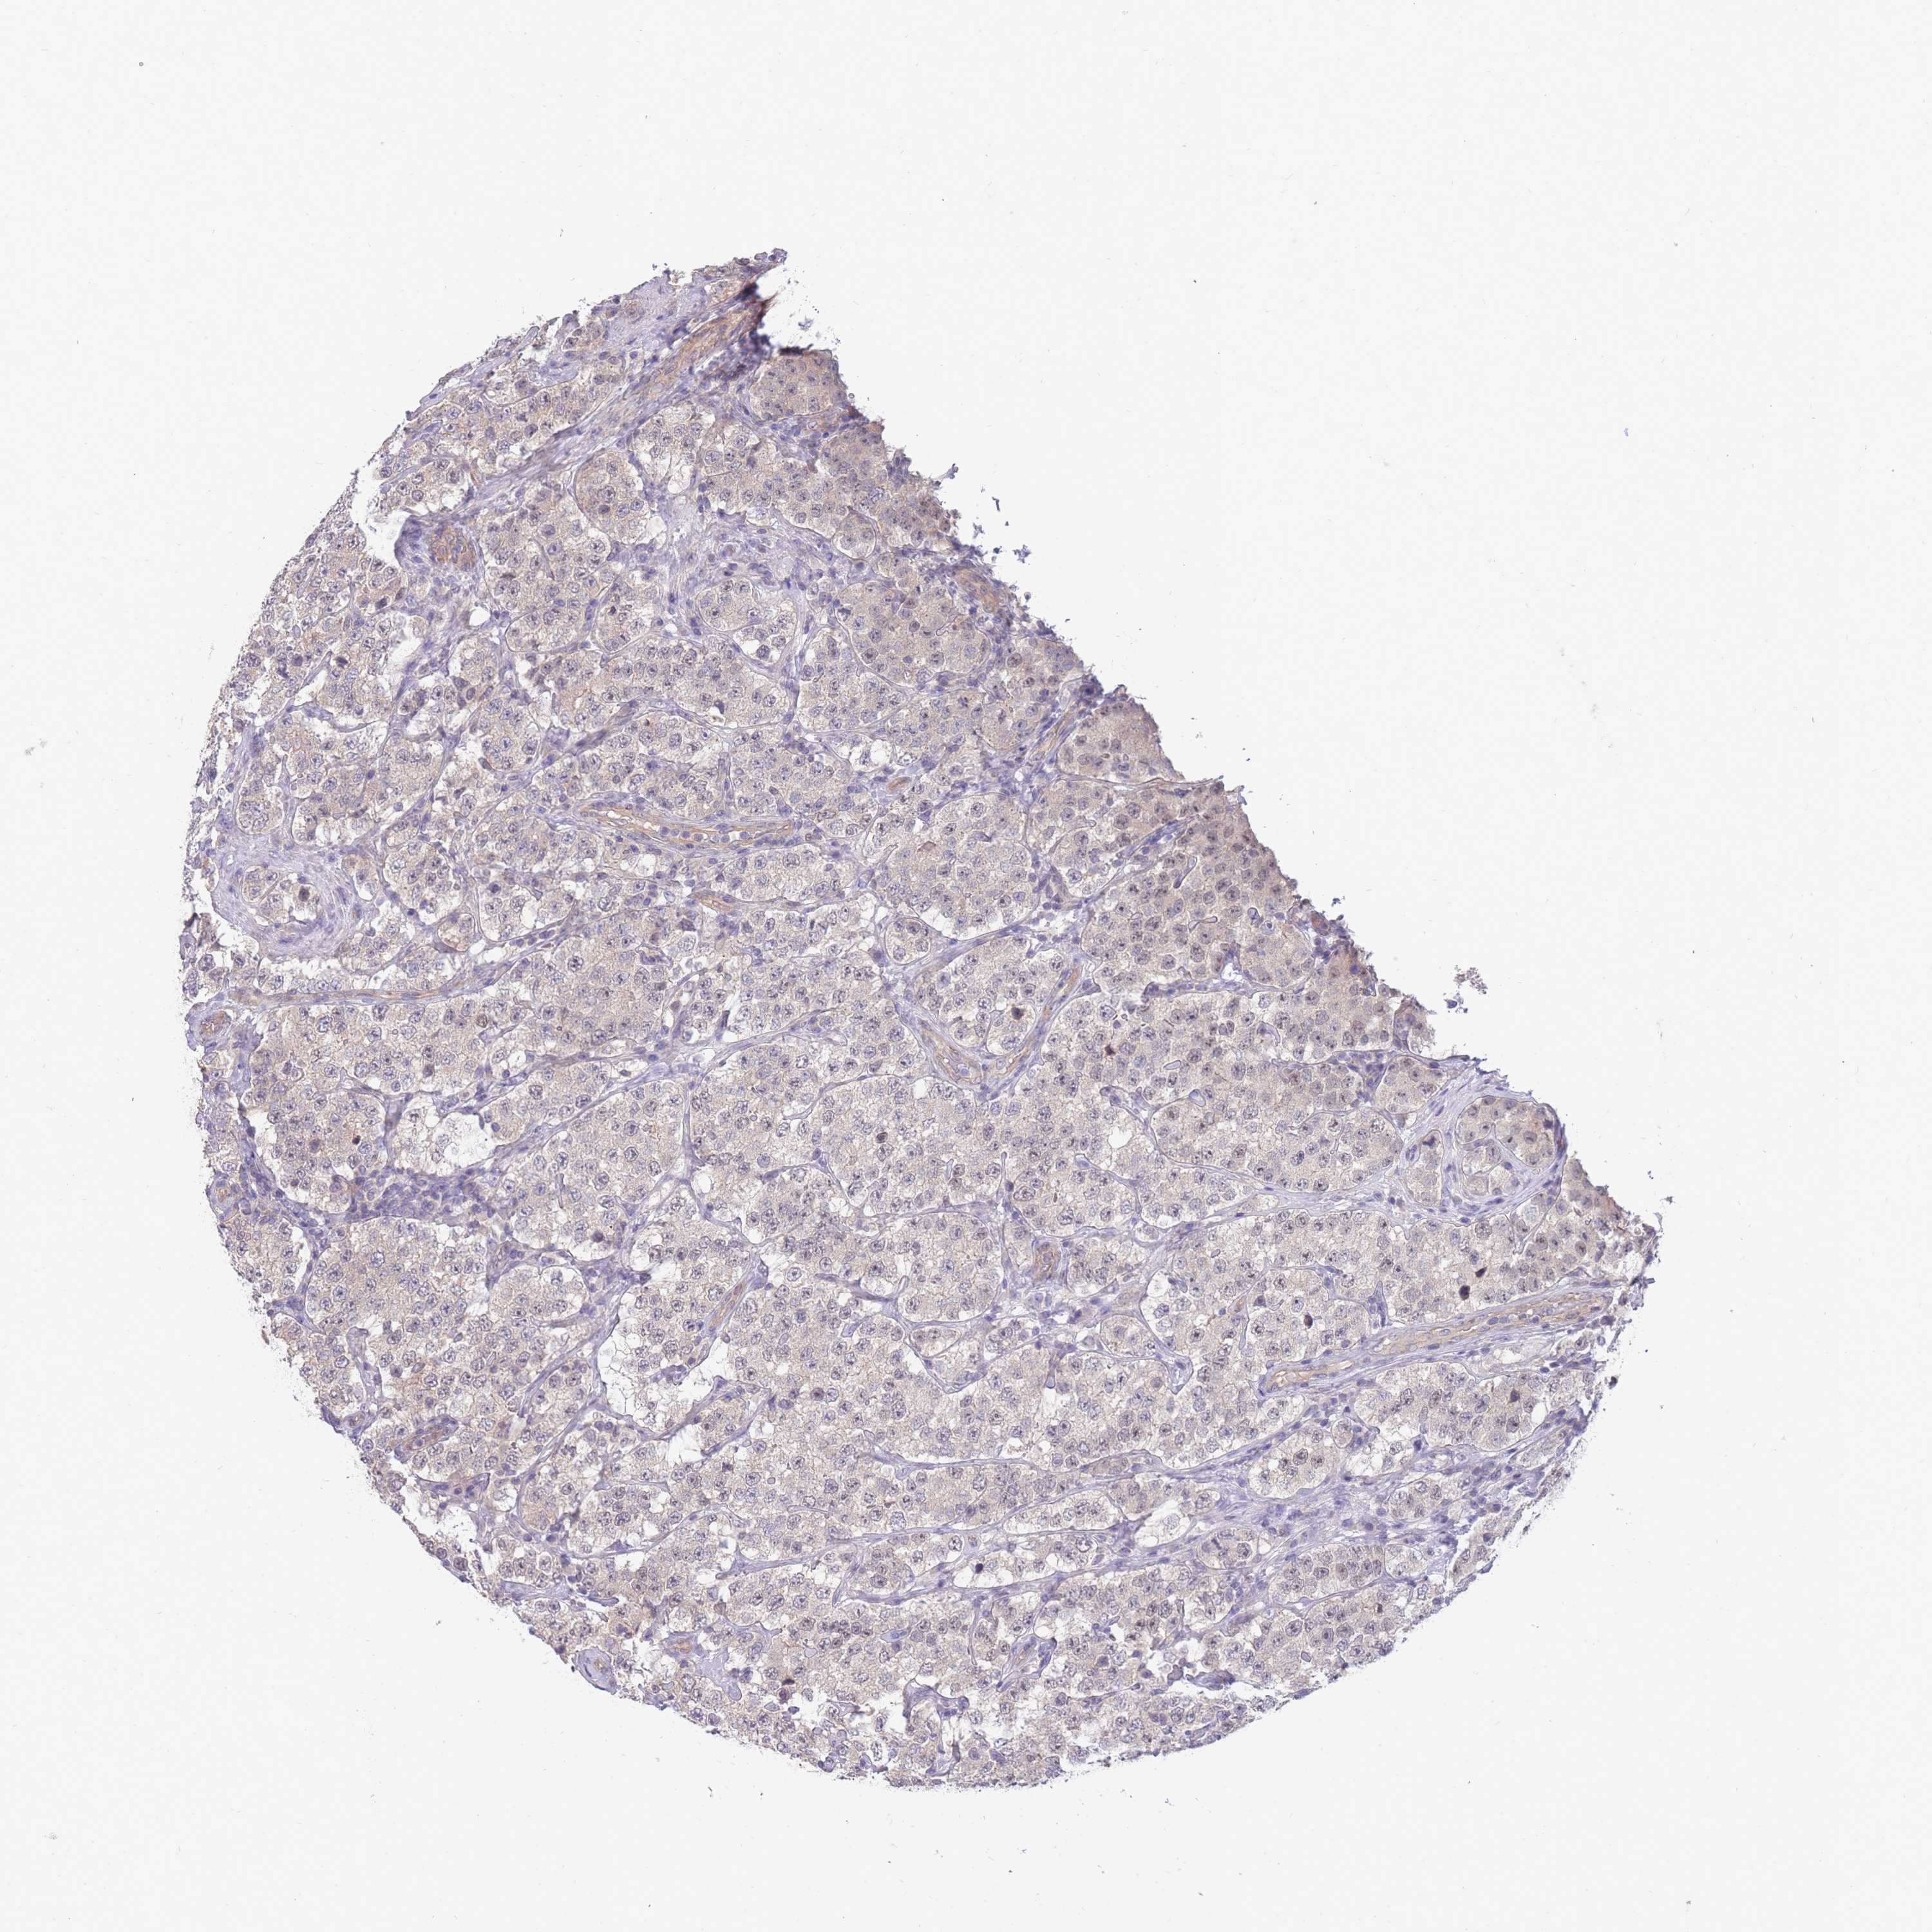

TESTIS CANCER - Protein expressioni

A mouse-over function shows sample information and annotation data. Click on an image to view it in a full screen mode. Samples can be filtered based on level of antibody staining by selecting one or several of the following categories: high, medium, low and not detected. The assay and annotation is described here.

Note that samples used for immunohistochemistry by the Human Protein Atlas do not correspond to samples in the TCGA dataset.

Antibody stainingi

Antibody staining in the annotated cell types in the current human tissue is reported as not detected, low, medium, or high, based on conventional immunohistochemistry profiling in selected tissues. This score is based on the combination of the staining intensity and fraction of stained cells.

Each image is clickable and will lead to virtual microscopy that enables deeper exploration of all samples and also displays staining intensity scores, fraction scores and subcellular localization as well as patient and tissue information for each sample.

Antibody HPA042733

Antibody CAB037186

Staining

High

Medium

Low

Not detected

Intensity

Strong

Moderate

Weak

Negative

Quantity

>75%

75%-25%

<25%

None

Location

Nuclear

Cytoplasmic/membranous

Cytoplasmic/membranous,nuclear

Carcinoma, Embryonal, NOS

Seminoma, NOS